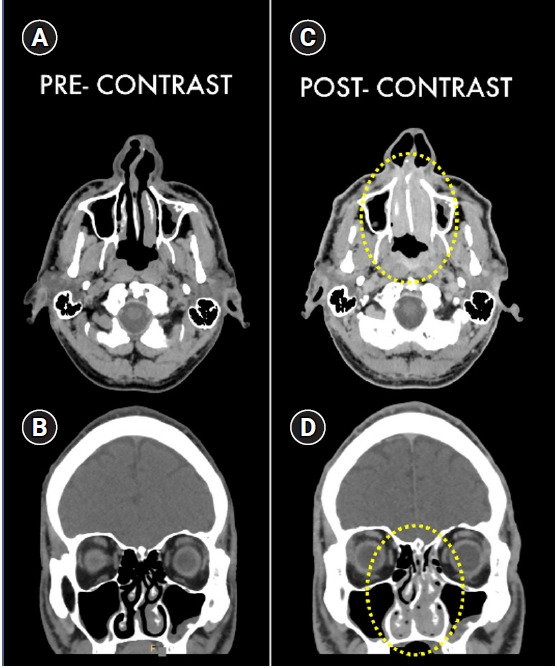

Computed tomography images of acute iodinate contrast medium reaction.

急性碘酸造影剂反应:查看 CT 图像!